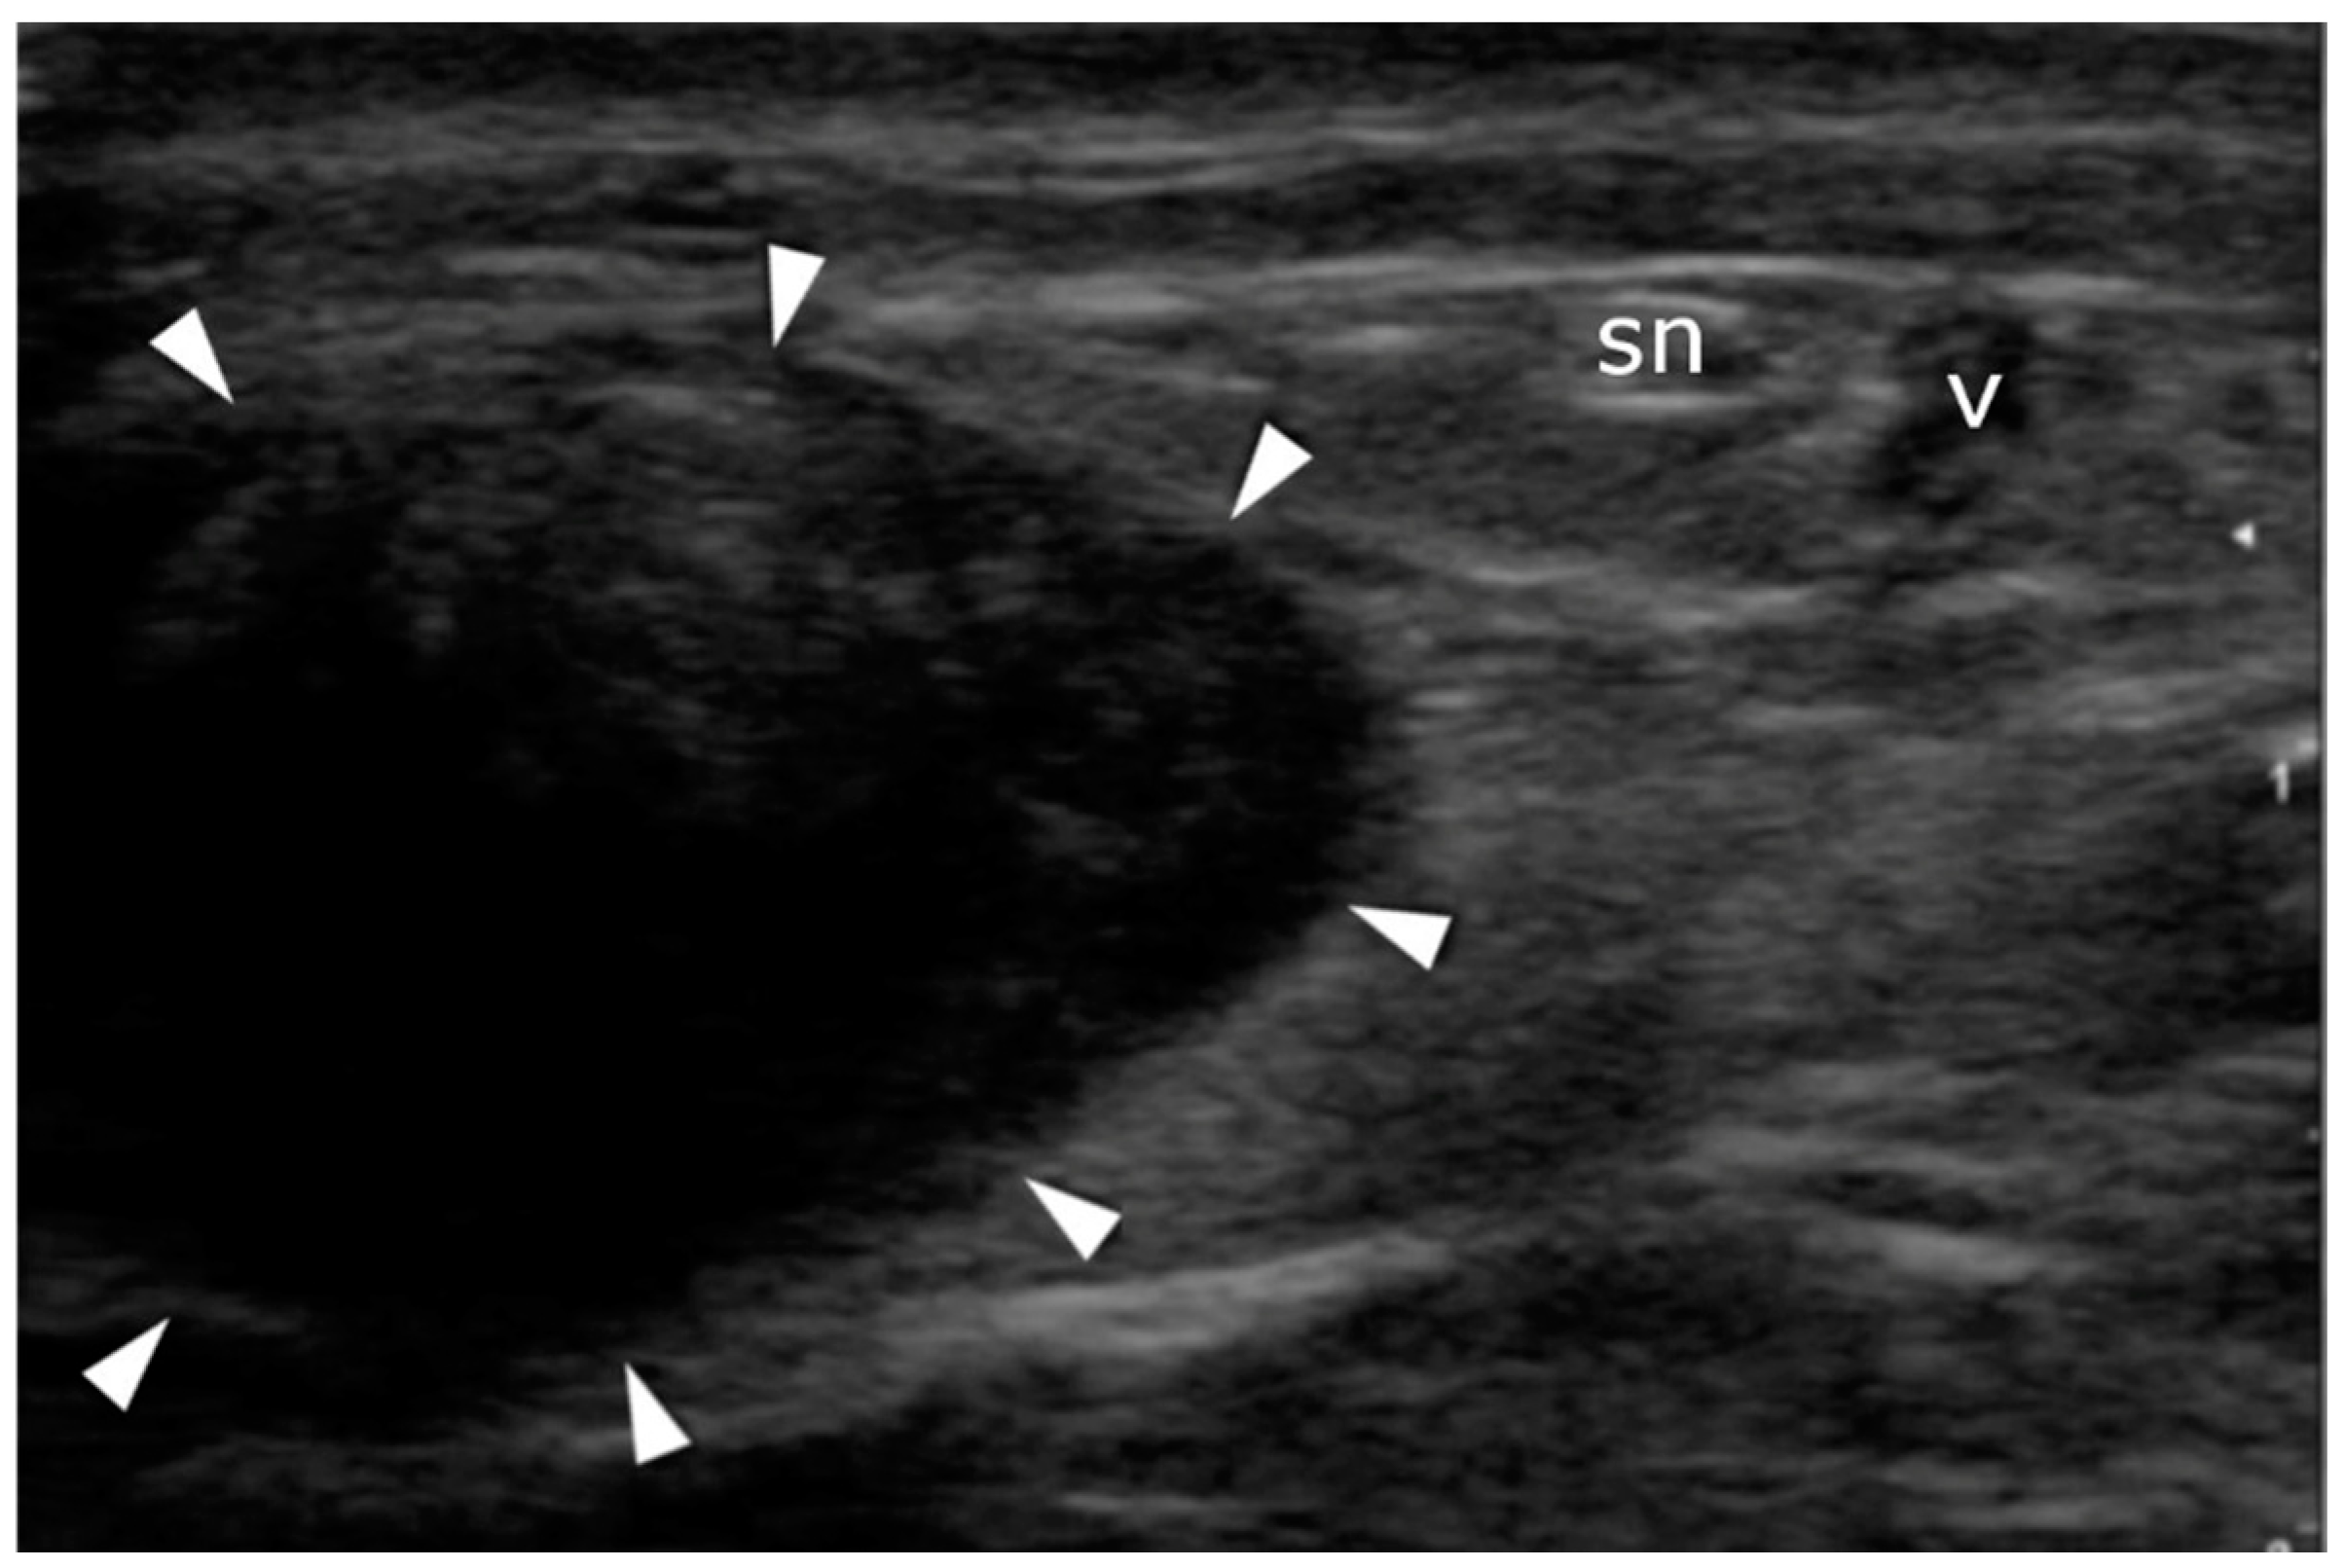

Figure 5.

Sural nerve identification: transverse plane. The nerve (sn) and vein (v) pass on the lateral side of the Achilles tendon (arrowheads).

A high-resolution real-time ultrasound examination was performed in the operation room. We used a sterile draped high-frequency (10–12 MHz) linear probe. Transverse scans were used to localize the SN. It was followed from the proximal area of the calf—where it laterally follows the saphenous vein in its fascial compartment between the two heads of the gastrocnemius—to the distal area and the lateral malleolus area. The SN’s echogenicity is oval and typical of nerves, showing hyperechogenic spots in the hypoechogenic area surrounded by the hyperechogenic sheath (Figure 5, Supplementary Material Video S1). The entry point and the angle of the needle were chosen with direct US guidance (Figure 6, Supplementary Material Video S2). The suture course was checked before it entered the skin incision (Figure 7, Supplementary Material Video S3).